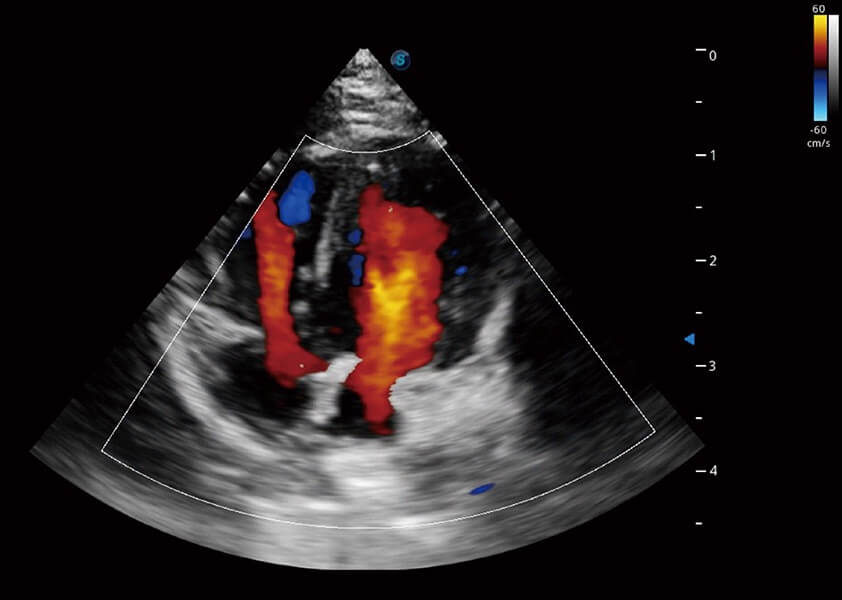

(犬)四腔心血流

心脏解决方案

ProPet 60 配备了丰富的心脏探头群、先进的成像技术和专业的心脏测量工具,可帮助动物医生为不同体型和生理结构的动物提供心脏和心肌功能的全面评估。

• TDI 组织多普勒成像

实时用颜色表示心肌组织运动,观察和定量组织的运动情况,对快速检测与评估心肌的灌注和活性、电传导及心肌收缩和舒张功能等均能提供重要的诊断信息。

• MQA 心肌定量分析

通过心肌识别技术与二维斑点追踪技术相结合,对心脏的超声图像进行量化分析。计算心肌17个节段的应变、应变率、速度、位移等,并通过牛眼图的形式进行呈现。

(犬)心脏组织多普勒